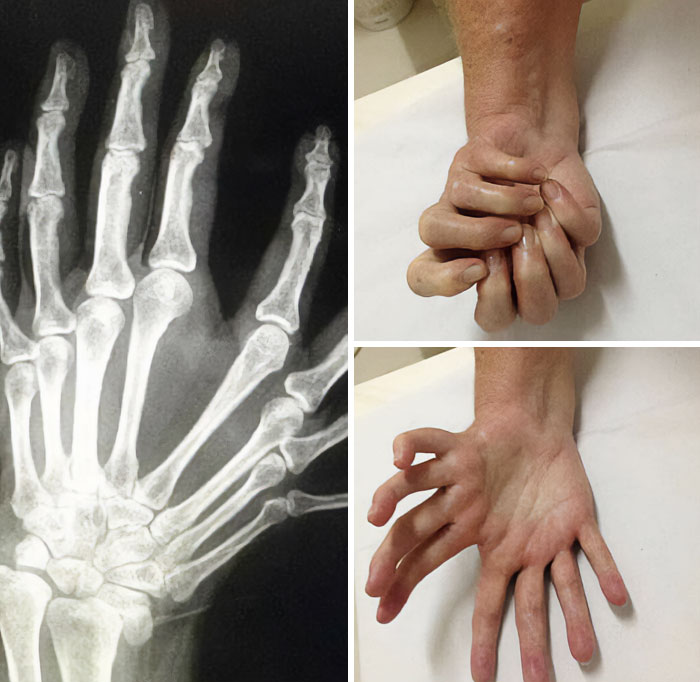

This Condition Is Called Mirror Hand Syndrome, Less Than 100 Cases Have Ever Been Diagnosed And The Cause Is Still Unknown

Triphalangeal Thumb (Tpt) Is A Congenitalmalformation Where The Thumb Has Three Phalanges Instead Of Two. The Extra Phalangeal Bone Can Vary In Size From That Of A Small Pebble To A Size Comparable To The Phalanges In Non-Thumb Digits